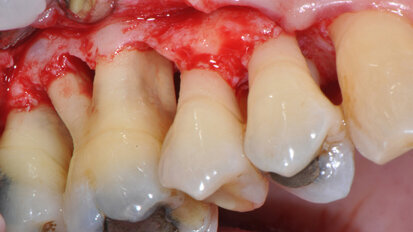

Il controllo chimico della placca nella terapia delle malattie parodontali e perimplantari placca-indotte

Le patologie infettive che colpiscono i tessuti parodontali e perimplantari hanno un comune primum movens eziopatogenetico: l’accumulo di placca ...